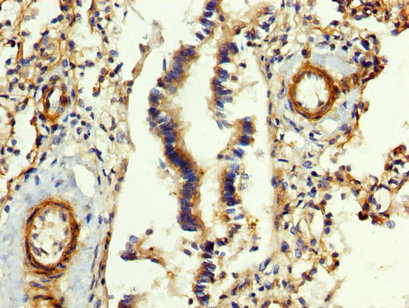

IHC image of CSB-PA008608LA01HU diluted at 1:400 and staining in paraffin-embedded human lung tissue performed on a Leica BondTM system. After dewaxing and hydration, antigen retrieval was mediated by high pressure in a citrate buffer (pH 6.0). Section was blocked with 10% normal goat serum 30min at RT. Then primary antibody (1% BSA) was incubated at 4°C overnight. The primary is detected by a biotinylated secondary antibody and visualized using an HRP conjugated SP system.